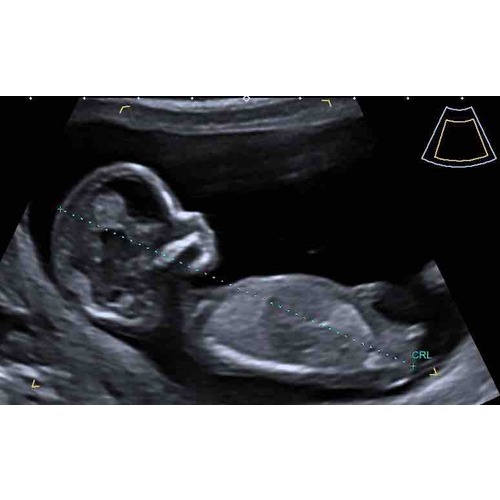

Hoi nubster🙂 ik heb nog 2 andere echo foto’s. Misschien zijn deze iets duidelijker? Baby’tje ligt wel ietsjes naar z’n linkerzijde

En de 2e foto

@nubster ik heb er nog 3 maar daarna is het ook echt gedaan dus dan moet ik maar wachten tot de nipt terug komt 🙈🙈

2

3

Hier nog wat foto’s🙂